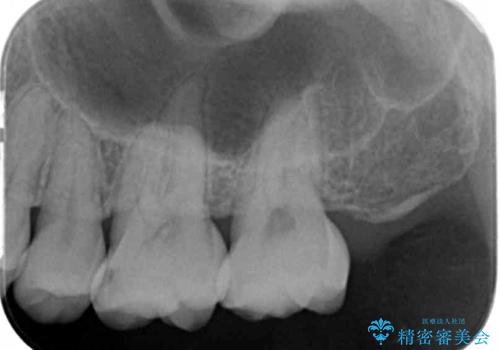

歯と歯の間の虫歯 ゴールドインレーでの修復

- フロスがよく詰まるところがあるとのことで来院されました。

検査の結果、左上の奥歯に虫歯があることが確認されました。

見た目よりも精度を優先したいとのことだったため、ゴールドインレーでの修復処置を行いました。

ゴールドの修復物は高い精度を出すことができるため非常に適合の良いものを装着することができます。